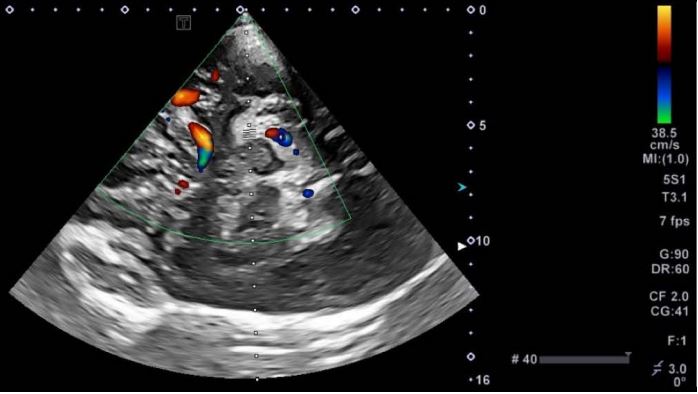

Режим КДК та режим ADF (Розширений динамічний потік)

Притаманна техніці проблема кольорового доплерівського картування в тому, що нерідко виникає спотворюючий ефект на зображенні, оскільки на нього впливає фоновий шум. Фоновий шум, який дотепер лише частково усувався засобами фільтрів низьких частот.

Як ви можете бачити в цьому випадку (Мал. 4), морфологічний діаметр зображення в техніці кольорового та енергетичного доплера не представлений морфологічним дослідженням у B-режимі (Мал. 3). Розвиток досліджень у Bрежимі також дозволив правильно ідентифікувати техніку як ТК ВС.

Малюнок 3

Малюнок 4